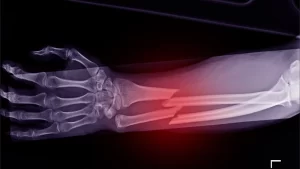

3. Fracture Management

The treatment of bone fractures at all levels from basic cracks to complicated breaks involves using casting, splinting, and surgical fixation methods. The treatment approach for fractures depends on their location and the fracture type to achieve proper healing and bone strength recovery.